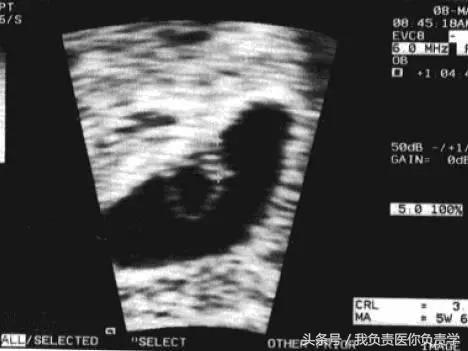

一旦超声观察到了胚芽,就可以测量头臀长(CRL),CRL 是估计孕龄的最佳方法之一,但是该指标仅适用于早孕期,在中期妊娠中双顶径(BPD)和头围(HC)被认为与孕龄密切相关。一般情况下可以按照「孕周 = 胚胎头臀长(cm)+6.5」来估算孕周。

妊娠 6 周,胚芽贴附在卵黄囊上